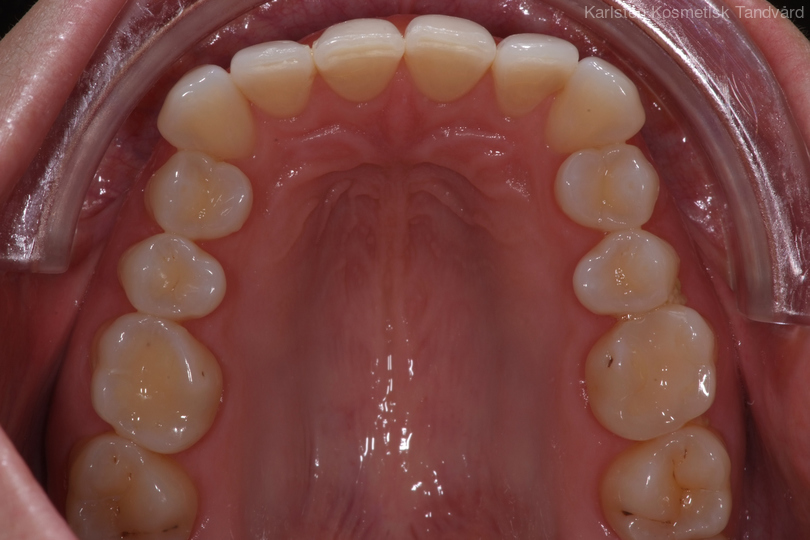

32-årig kvinna som tycker att hon bara visar sina framtänder. En utjämning och vidgning av tandbågen med 8 månaders genomskinliga Invisalignskenor, gav henne ett fint leende.